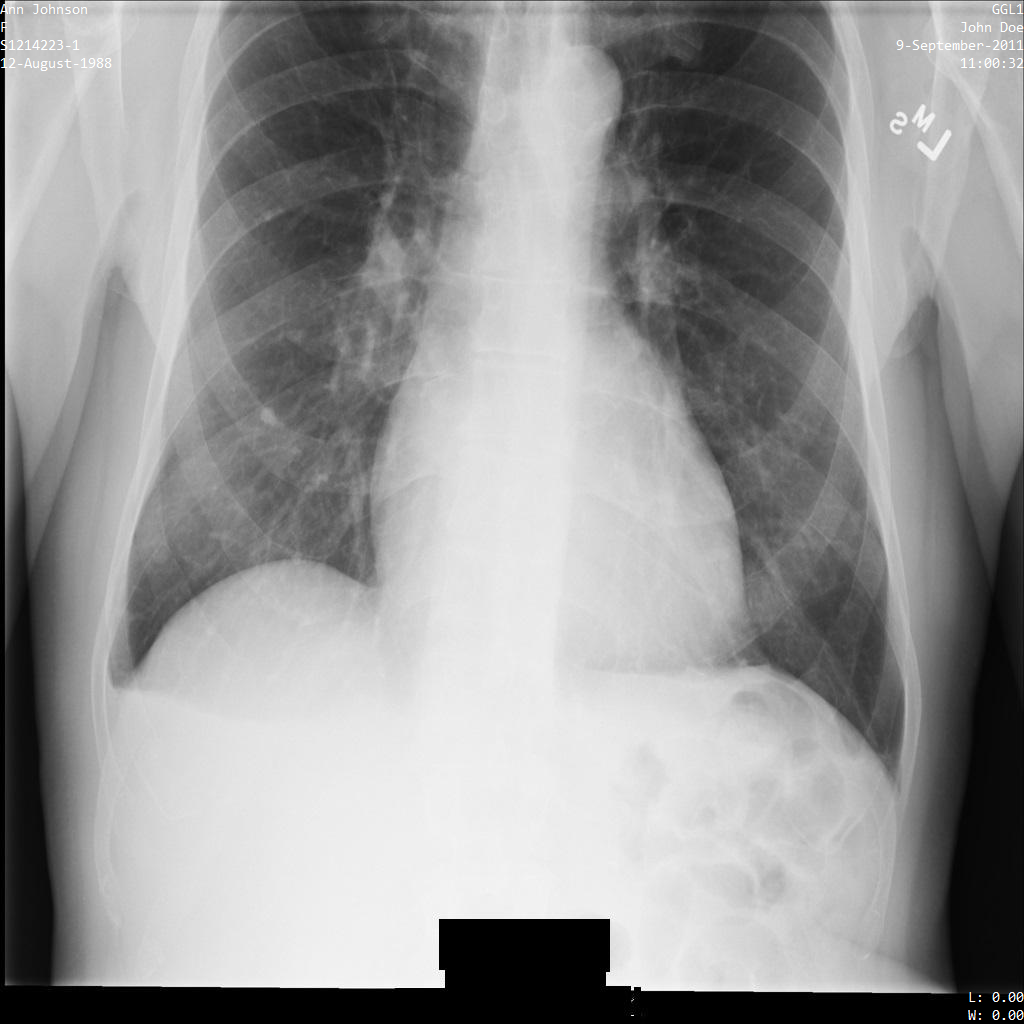

In jedem der folgenden Abschnitte finden Sie Beispiele zur De-Identifikation von DICOM-Daten mithilfe verschiedener Methoden. Für jedes Beispiel wird eine Ausgabe des de-identifizierten Images bereitgestellt. In jedem Beispiel wird das folgende Originalbild als Eingabe verwendet:

Sie können das Ausgabebild jedes De-Identifizierungsvorgangs mit diesem Originalbild vergleichen, um die Auswirkungen des Vorgangs zu sehen.

Nachdem Sie das Image an die Cloud Healthcare API gesendet haben, wird es wie folgt angezeigt. Während die Metadaten, die in den oberen Ecken des Bildes angezeigt werden, entfernt wurden, bleiben die eingebrannten geschützten Gesundheitsinformationen (PHI) unten im Bild erhalten. Informationen zum Entfernen des eingebrannten Texts finden Sie unter Eingebrannten Text aus Bildern entfernen.